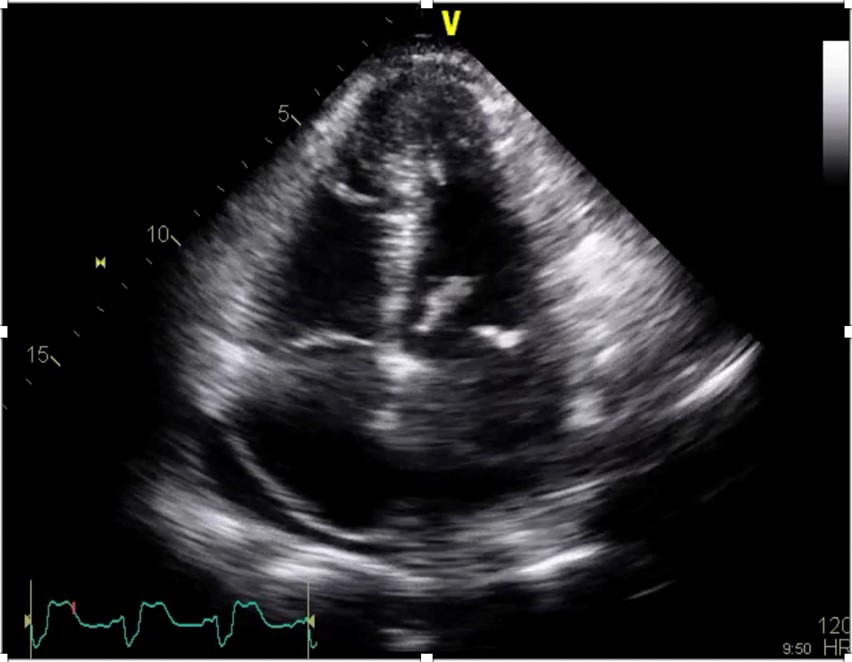

A point-of-care ultrasound was performed to help differentiate the cause of hypoxia and hypotension. The findings were consistent with the sequela of the patients recent RCA occlusion which demonstrated a newly identified flail posterior mitral valve leaflet and severe mitral regurgitation (Figures 1, 2, and 3). Subsequently, the patient was taken emergently to the cath lab for placement of an intra-aortic balloon pump (IABP). The balloon pump was adjusted to maximize the diastolic augmentation and minimize pre-systolic LV afterload to optimize the patient’s cardiac function.1 Once he was stabilized, the patient was taken to the operating room for a mitral valve replacement. After a prolonged hospital course, the patient survived to discharge and was sent to a skilled nursing facility for cardiac rehabilitation.

Figure 1. Apical 4 chamber view of a flail posterior mitral valve leaflet.